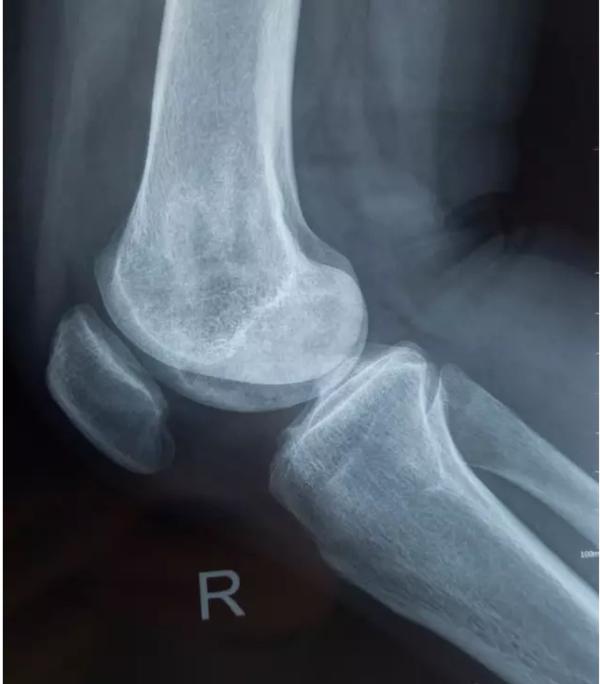

膝关节不均匀沉降术后患者X线片(下图)